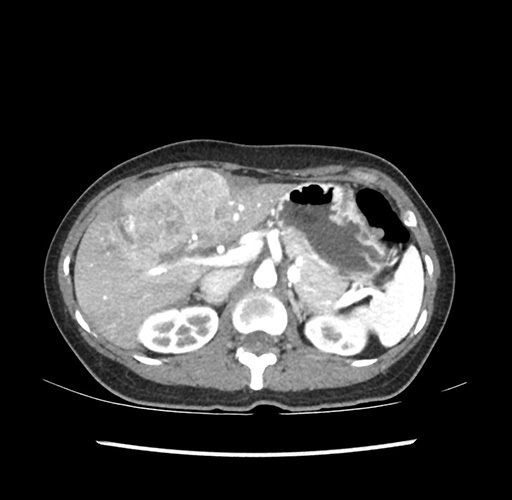

Imaging Analysis

Look through the patient's CT scan to identify any areas of concern for the necessary procedure.

Based on your CT findings, which issue(s) would give reason for "planned slowing down moment(s)" in this case?

Considering a standard left lateral sectionectomy procedure, what step(s) of the operation would you do differently in this case ?